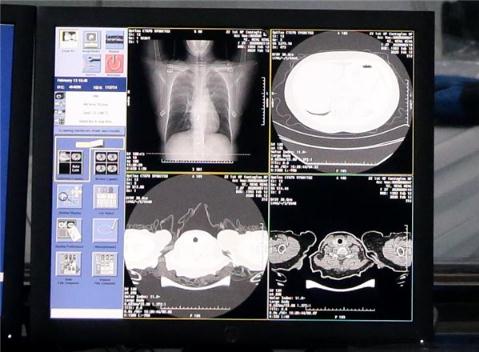

記者從阿里達(dá)摩院獲知,達(dá)摩院最新 AI 算法診斷技術(shù)可在 20 秒內(nèi)對(duì)新冠疑似案例 CT 影像做出判讀,分析結(jié)果準(zhǔn)確率達(dá)到 96%。該算法輔助診斷技術(shù)將在 2 月 16 日起在河南鄭州小湯山啟用。

根據(jù)國家衛(wèi)健委公布的診療方案第五版,臨床診斷無需依賴核酸檢測(cè)結(jié)果,CT 影像臨床診斷結(jié)果可作為新冠肺炎病例判斷的標(biāo)準(zhǔn)。新冠肺炎患者的 CT 的影像特征表現(xiàn)為單肺或雙肺多發(fā)、斑片狀或節(jié)段性磨玻璃密度影等細(xì)微變化。

據(jù)阿里達(dá)摩院介紹,達(dá)摩院醫(yī)療 AI 團(tuán)隊(duì)基于當(dāng)前最新的診療方案、鐘南山等多個(gè)權(quán)威團(tuán)隊(duì)發(fā)表的關(guān)于新冠肺炎患者臨床特征的論文,與多家機(jī)構(gòu)合作,基于 5000 多個(gè)病例的 CT 影像樣本數(shù)據(jù),學(xué)習(xí)訓(xùn)練樣本的病灶紋理,研發(fā)全新的 AI 算法模型。通過 NLP 自然語言處理回顧性數(shù)據(jù)、使用 CNN 卷積神經(jīng)網(wǎng)絡(luò)訓(xùn)練 CT 影像的識(shí)別網(wǎng)絡(luò),AI 可以快速鑒別新冠肺炎影像與普通病毒性肺炎影像的區(qū)別,最終識(shí)別準(zhǔn)確率高達(dá) 96%。AI 每識(shí)別一個(gè)病例平均只需要不到 20 秒,大大提高診斷效率,減輕醫(yī)生壓力。

達(dá)摩院透露,除了率先落地的河南鄭州小湯山醫(yī)院,AI 算法輔助診斷還將在湖北、廣東、安徽等地近 100 家醫(yī)院落地。